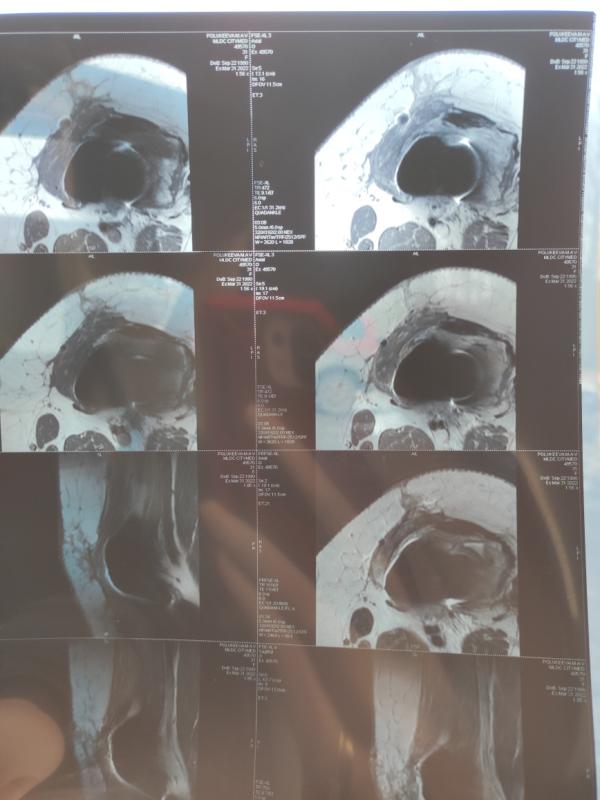

Не долго длилась моя спокойная жизнь. С момента операции прошло 2 месяца. И новый удар. Проходила обследование для МСЭ, сделали узи мягких тканей, обнаружили очаг. Вчера было МРТ. По результату новая опухоль 2×1.8 см,в мягких тканях, вдоль рубца. У меня шок. Я только думала что все закончилось. Видимо вселенная решила все за меня. 6 иду к онкологу. В Москве лечащий врач сказал нужно делать биопсию. Опять новые круги ада, ожидания, бесконечные консилиумы, приемы, анализы. Как же я от всего устала...